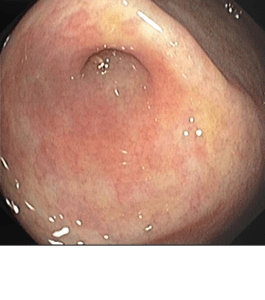

- Tumores: Masas anormales que pueden afectar los vasos sanguíneos o indicar la presencia de cáncer.